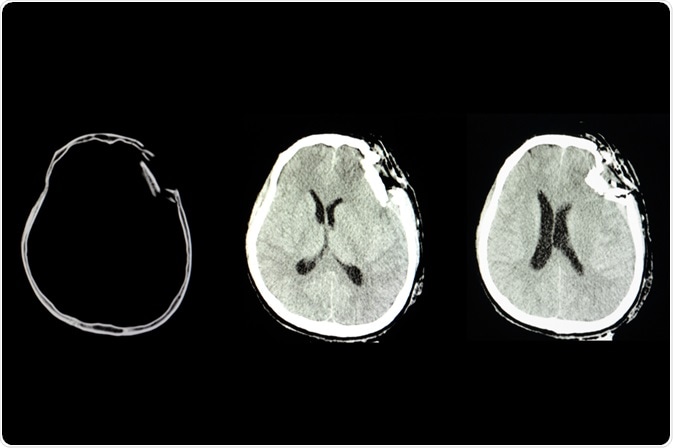

Traumatic Brain Injury

Image Credit: Tomatheart/Shutterstock.com